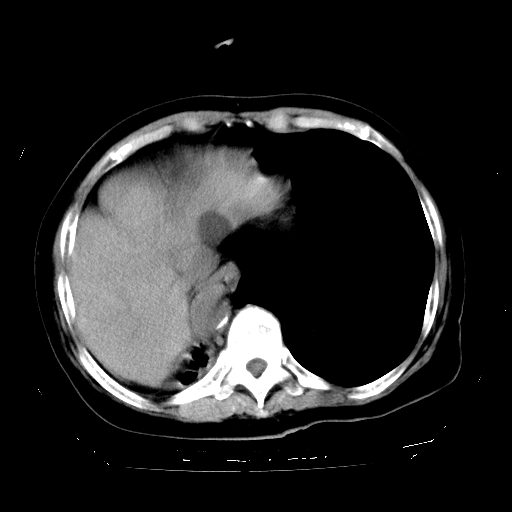

标题: CT23991:女,72岁,咳嗽、憋气一周。 [打印本页]

女,72岁,咳嗽、憋气一周,十年前曾患肺结核及胸膜结核。

1.右侧损毁肺伴胸膜钙化,2.左肺小结节灶,良性可能大,注意复查。3.肝脏左叶囊肿。4.先天性一侧肺不发育待出外(右侧胸廓无明显塌陷)。对比原片应该非常有帮助。